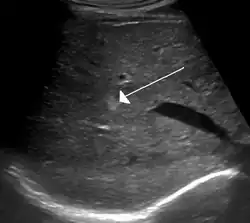

| Hemangioma em uma menina de 2 anos. | |